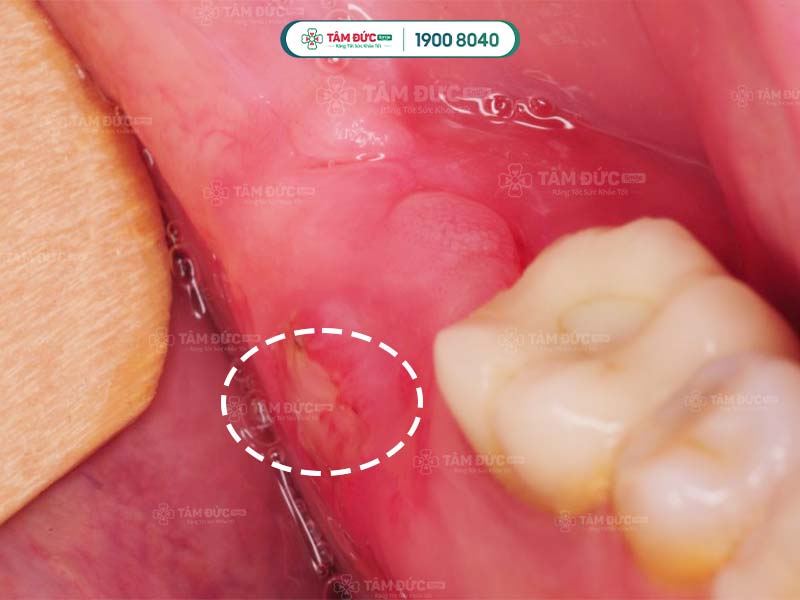

Áp xe răng khôn là thuật ngữ dùng để chỉ răng khôn (răng số 8) bị nhiễm trùng nghiêm trọng, có ổ mủ hình thành ở chân răng. Ở một số trường hợp, ổ mủ xuất hiện trong nướu hoặc cổ răng. Bác sĩ khẳng định, áp xe răng khôn chính là hệ quả của tình trạng viêm nướu, viêm tủy, sâu răng khôn,... không được điều trị kịp thời.

Vùng nướu ở vị trí răng khôn bị sưng đỏ, Quý khách có thể nhìn thấy mủ tích tụ bằng mắt thường.

Áp xe răng khôn khi răng mọc ngầm